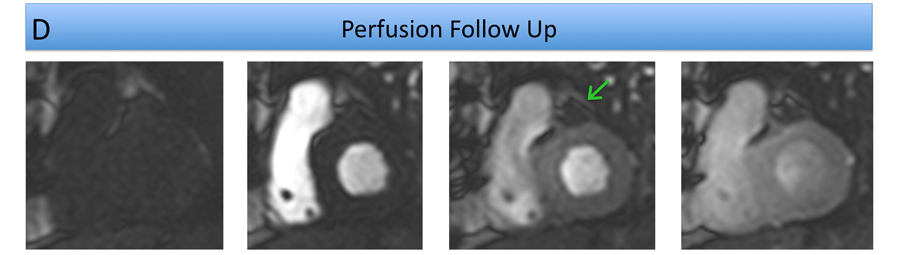

First pass perfusion demonstrated its communication with the aortic root but no extravasation of contrast into the pericardial space. There was also a small anterior transmural scar (Figure C, Video 1). During cardiac surgery a small, closed, dimple deep in a recess immediately above the annulus was visualized not needing further intervention (Figure B Follow Up CT arrow). On Follow Up CMR the structure did not show first pass perfusion and appeared to be thrombosed (Figure D, Figure E, Video 2). Diagnosis of a ruptured small aneurysm of the Sinus of Valsalva with extraaortic haematoma probably compromising a small branch coronary artery was made.